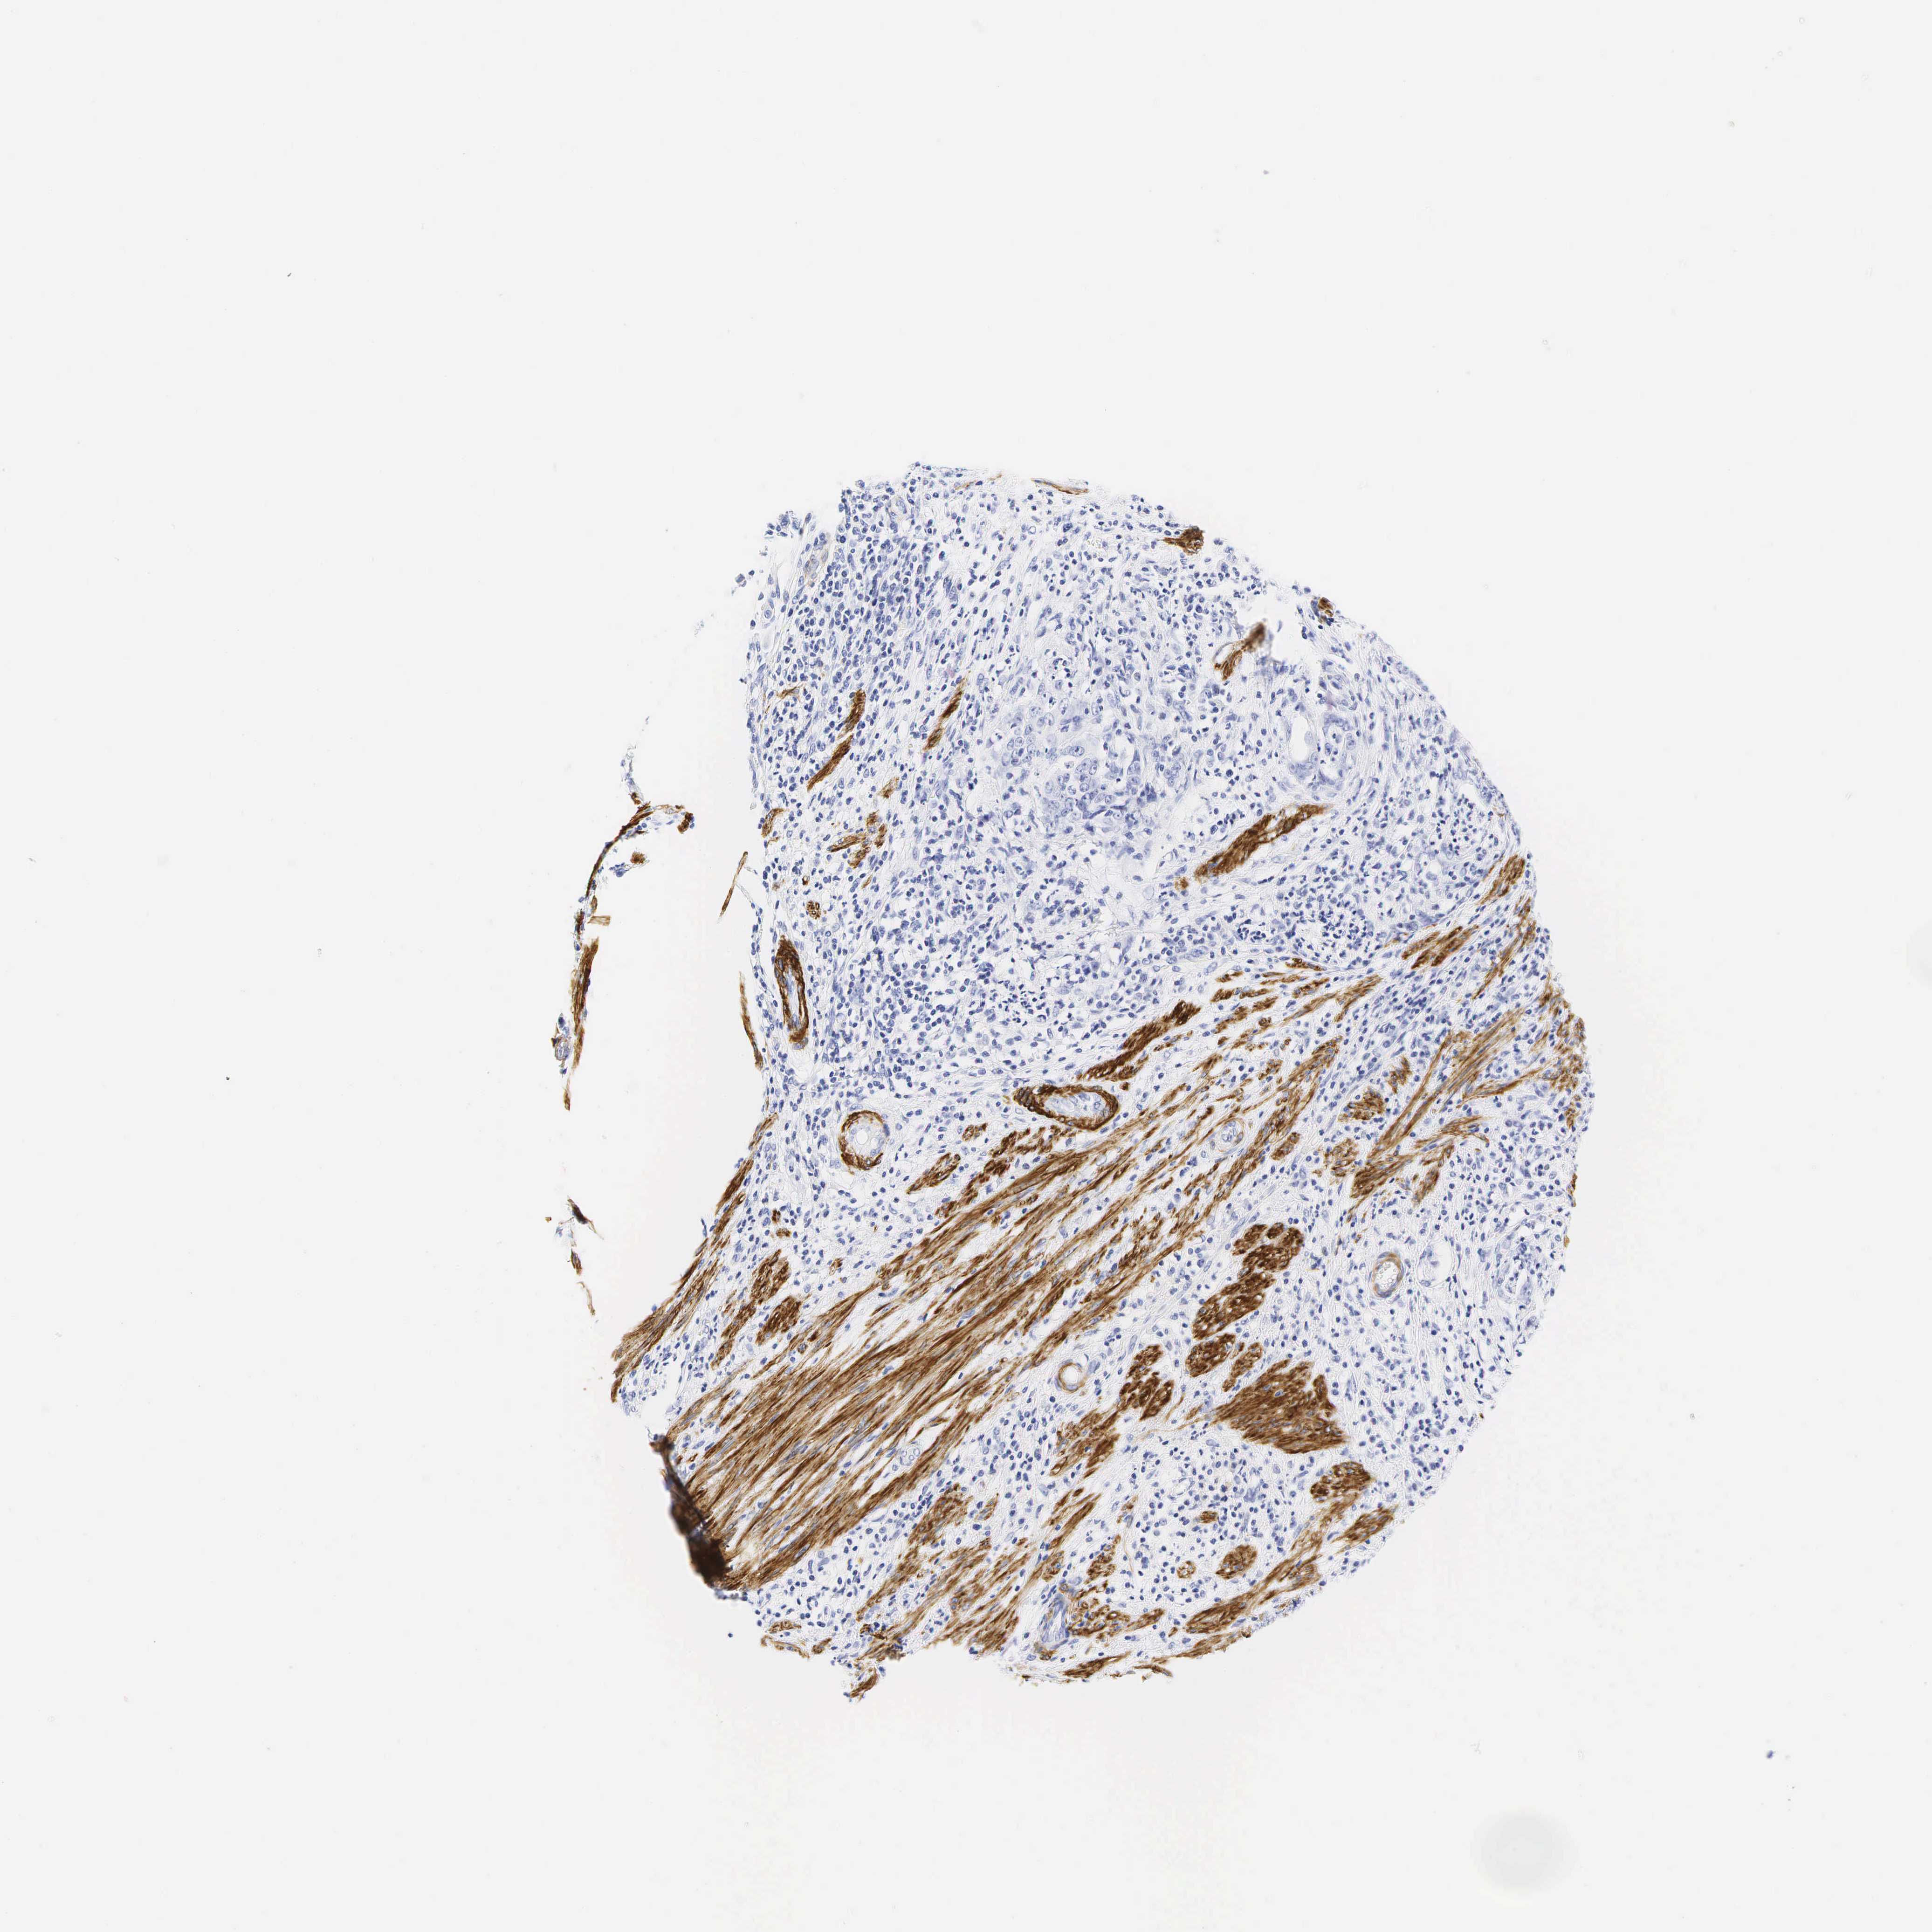

STOMACH CANCER - Protein expressioni

A mouse-over function shows sample information and annotation data. Click on an image to view it in a full screen mode. Samples can be filtered based on level of antibody staining by selecting one or several of the following categories: high, medium, low and not detected. The assay and annotation is described here.

Note that samples used for immunohistochemistry by the Human Protein Atlas do not correspond to samples in the TCGA dataset.

Antibody stainingi

Antibody staining in the annotated cell types in the current human tissue is reported as not detected, low, medium, or high, based on conventional immunohistochemistry profiling in selected tissues. This score is based on the combination of the staining intensity and fraction of stained cells.

Each image is clickable and will lead to virtual microscopy that enables deeper exploration of all samples and also displays staining intensity scores, fraction scores and subcellular localization as well as patient and tissue information for each sample.

Antibody HPA008066

Antibody HPA017330

Antibody CAB000006

Staining

High

Medium

Low

Not detected

Intensity

Strong

Moderate

Weak

Negative

Quantity

>75%

75%-25%

<25%

None

Location

Nuclear

Cytoplasmic/membranous

Cytoplasmic/membranous,nuclear

Adenocarcinoma, NOS